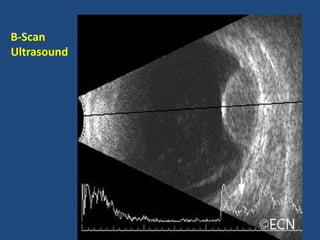

This document discusses symptoms of retinal disease such as blurred vision, visual distortions, and flashes of light. It also outlines examination techniques for evaluating the retina, including using direct and indirect ophthalmoscopes, slit lamps with specialized lenses, retinal photos, ultrasound, and angiography to visualize the retina and assess diseases.